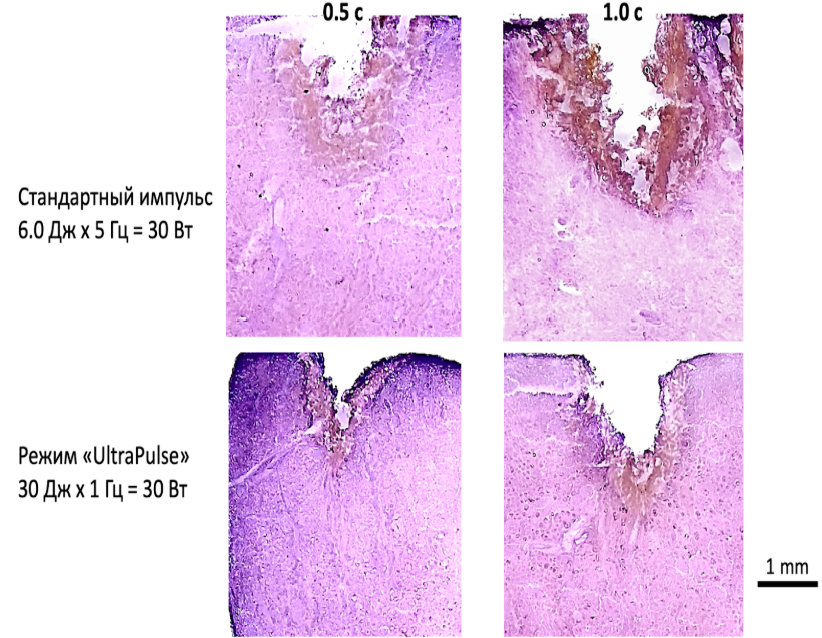

Режим “UltraPulse” - более безопасный по сравнению со стандартным импульсом при одинаковом уровне мощности: меньшее проникновение в ткани, менее травматичное рассечение в случае попадания импульса на мягкие ткани.